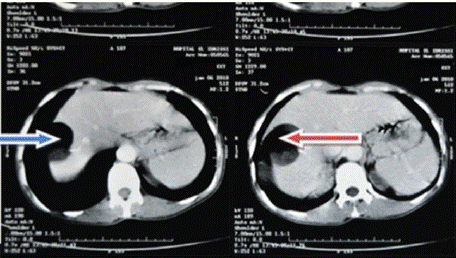

Figure 4: Red arrow: well-defined rounded lesion in segment VIII with

probable cystic NHA image.

Ultrasound of the right liver (anterior sector) revealed a heterogeneous cystic image with a thin wall, suggestive of a type IV hydatid cyst. Abdominal CT confirmed a multiloculated cystic lesion containing fatty, calcified, and fluid components, suggestive of a hepatic teratoma. An MRI scan further supported the diagnosis, showing a grossly oval lesion in the hepatic dome measuring 57 × 48 mm. The lesion contained a fluid level with a supernatant displaying T1 hypersignal, T2 hyposignal, and a dependent portion in T1 and T2 isosignal, without enhancement after gadolinium injection — findings suggestive of a modified hydatid cyst.